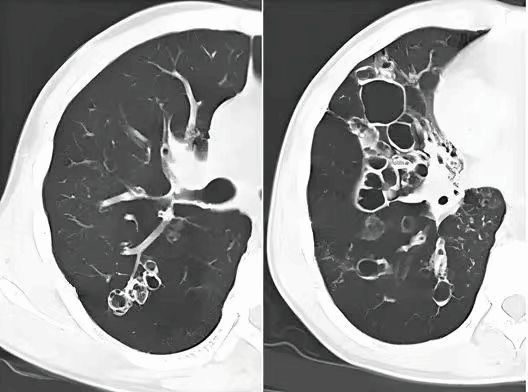

胸部CT检查:高分辨CT(HRCT)可在横断面上清楚地显示扩张的支气管,由于无创、易重复和易接受的特点,已成为支气管扩张的主要诊断方法。